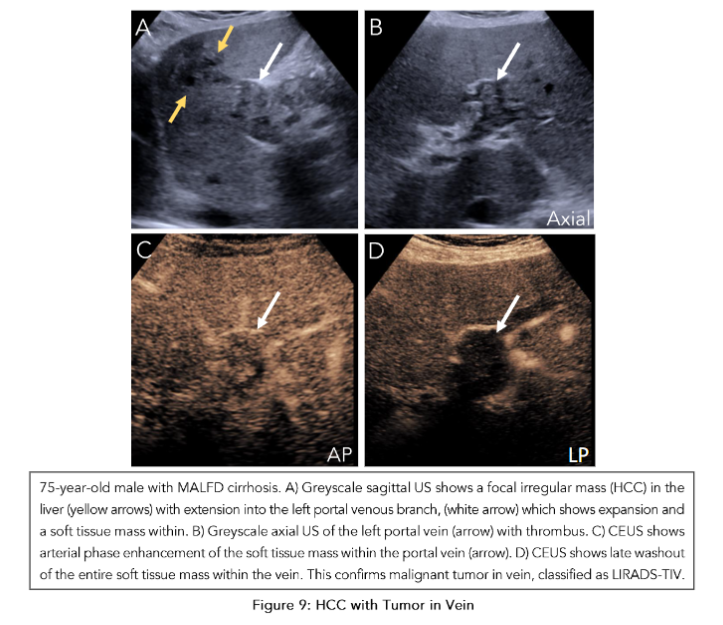

Beyond identifying the likely HCC correlates on ultrasound, CEUS can also reveal surprise findings that can change management. Potential surprise findings can include a size discrepancy or additional liver lesions not previously seen on prior MRI. Depending on the size and number of total lesions, ablation therapy may not be indicated(36). Although there is no universally agreed upon size cut-off, commonly cited thresholds include up to 5 cm for one unilobar lesion or 3 cm for multiple unilobar lesions(37). Furthermore, ablation may also not be indicated if there is any evidence of tumor in vein (TIV), which needs to be differentiated from a morphologically similar benign portal vein thrombus (PVT) (Figure 9). With an incidence of 9.8% in patients with cirrhosis, PVT is a relatively common complication that can be present in the patient population undergoing pre-ablation planning CEUS.

Figure 9: HCC with Tumor in Vein